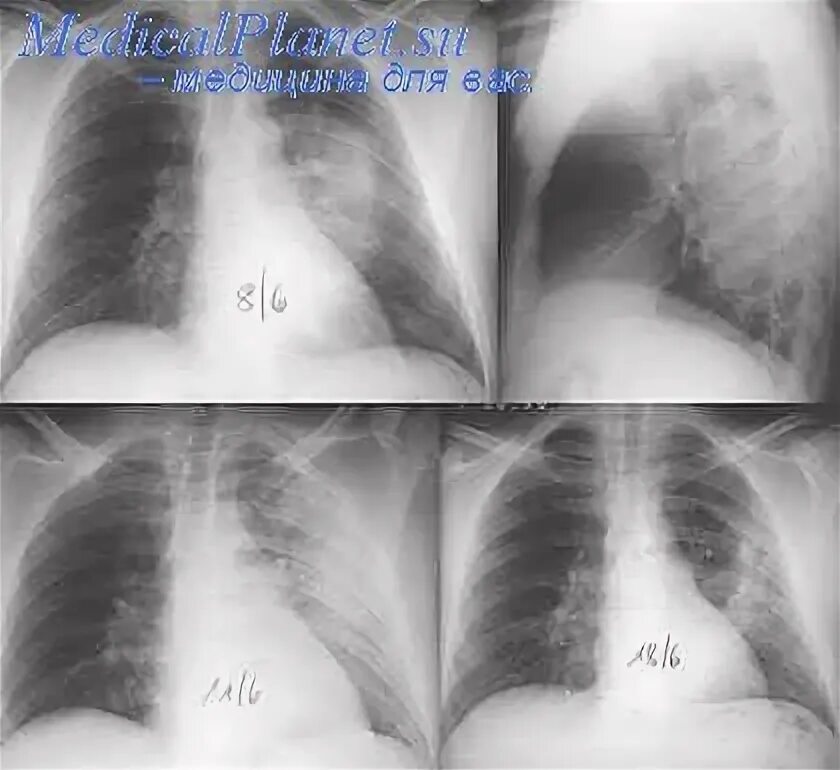

Пневмония 9 сегмента

Сегментарная пневмония s3. левосторонняя полисегментарная пневмония рентген. сегментарная пневмония рентген. сегментарная пневмония s 6.

Левосторонняя полисегментарная пневмония рентген. правосторонняя очаговая пневмония рентген. правосторонняя сегментарная пневмония рентген. сегментарная пневмония у детей рентген.

Рентгенологические критерии пневмонии. рентгенологическая классификация пневмоний. рентгенологическая характеристика пневмонии. сегментарная пневмония рентгенологические признаки.

Правосторонняя сегментарная пневмония s2,. сегментарная пневмония на рентгенограмме. сегментарная пневмония рентген. пневмония сегменты.

Сегментарная пневмония рентген. полисегментарная пневмония рентген. рентген легких полисегментарная пневмония. сегментарная пневмония у детей рентген.